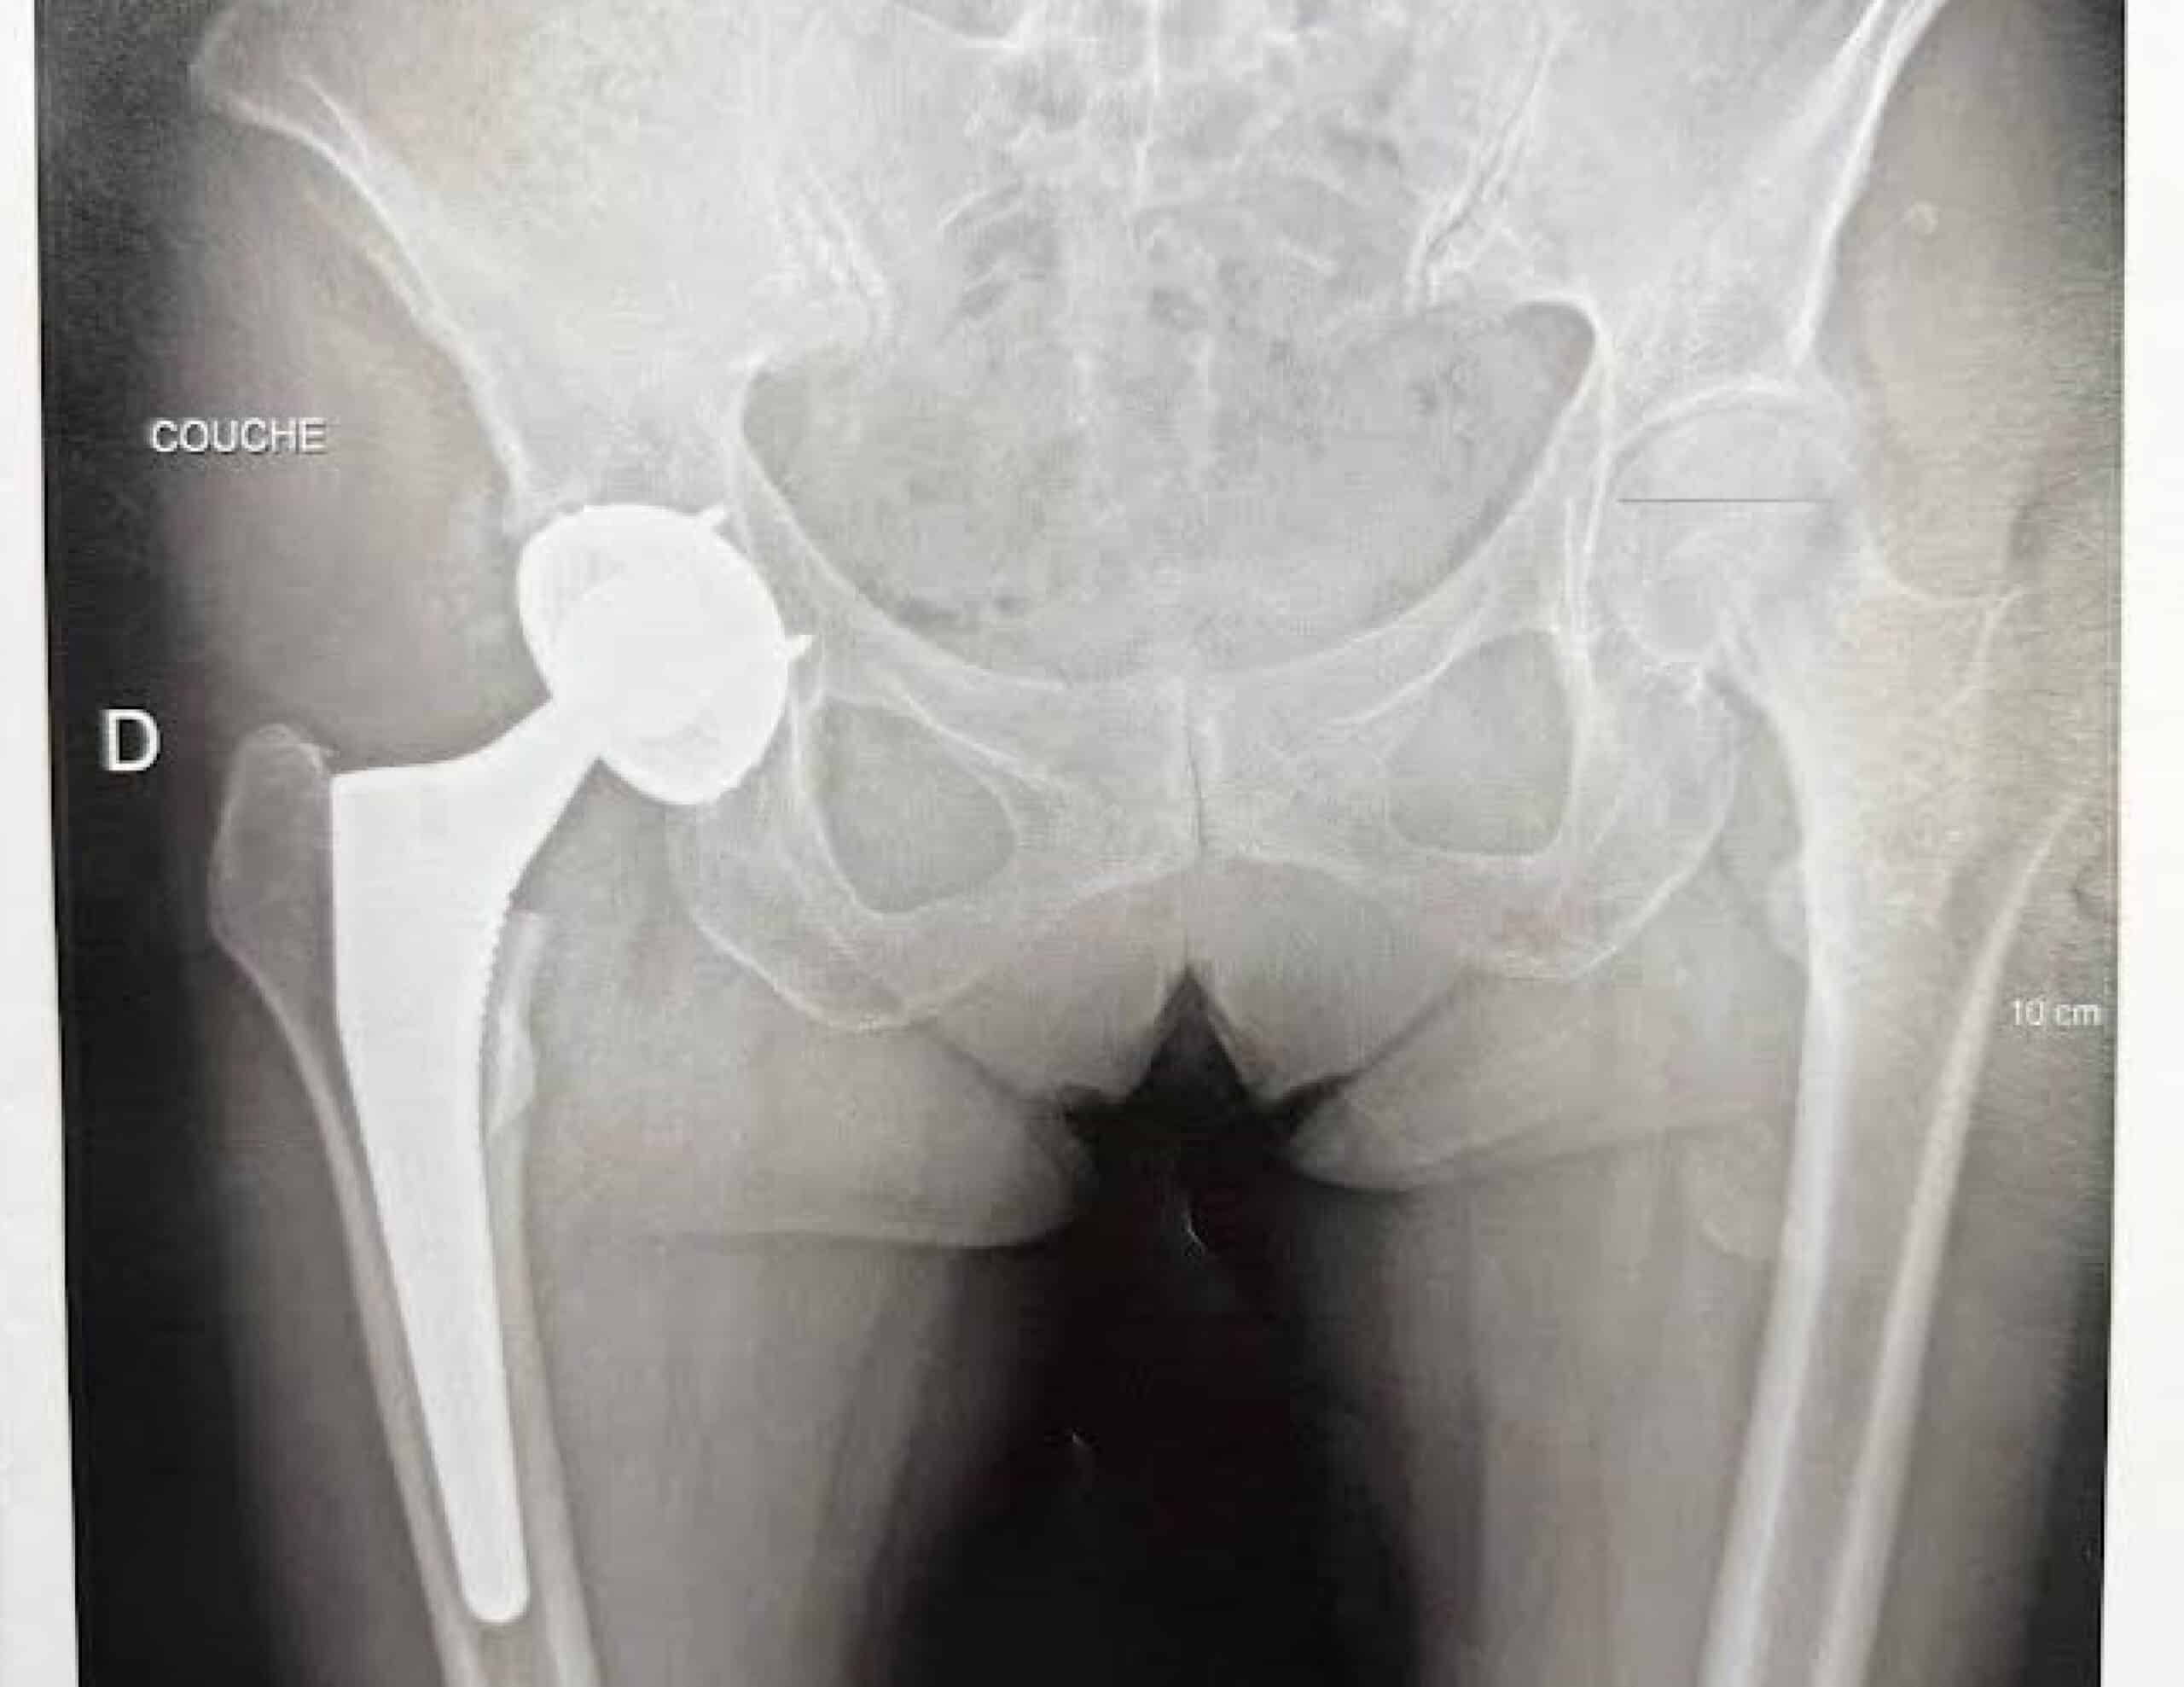

Le bilan d’imagerie doit permettre de quantifier l’inégalité de longueur. Il faut retrouver des radiographies du bassin debout de face, réalisées avant et après l’implantation prothétique.

Un bilan EOS (imagerie du rachis et des membres inférieurs en entier, debout) permet de mesurer la longueur des segments osseux et de quantifier le déséquilibre lombo-pelvi-fémoral. Mais l’examen de référence reste l’ imagerie 3D scanner.

Grâce à une analyse tridimensionnelle au scanner, on pourra diagnostiquer une malposition de la cupule, une malposition de la tige fémorale, ou un mauvais réglage des tensions articulaires liés au choix de la tête prothétique.